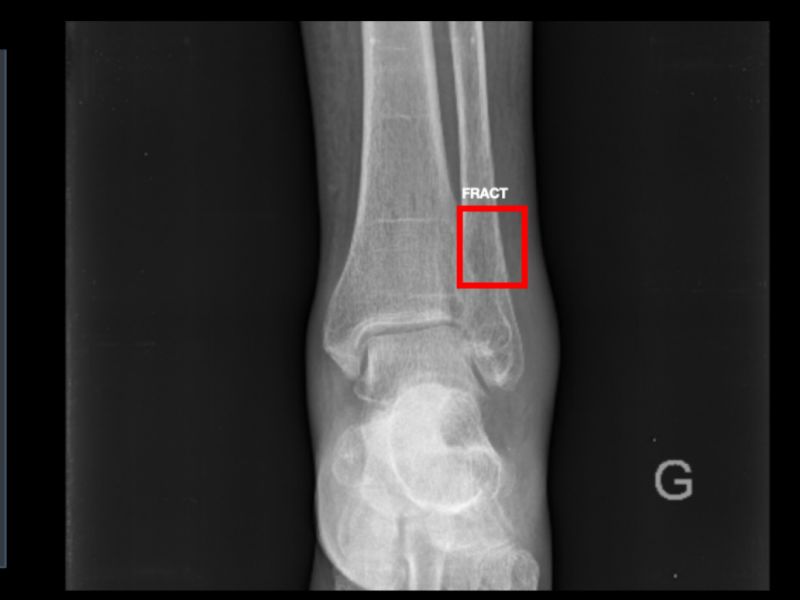

Votre assistant AI pour les radiographies des traumatismes osseux.

Précis

99,7% de valeur prédictive négative.

Complet

Diagnostic automatisé et comptes rendus détaillés.

Efficace

La solution réduit le risque de manquer des fractures de 30%.